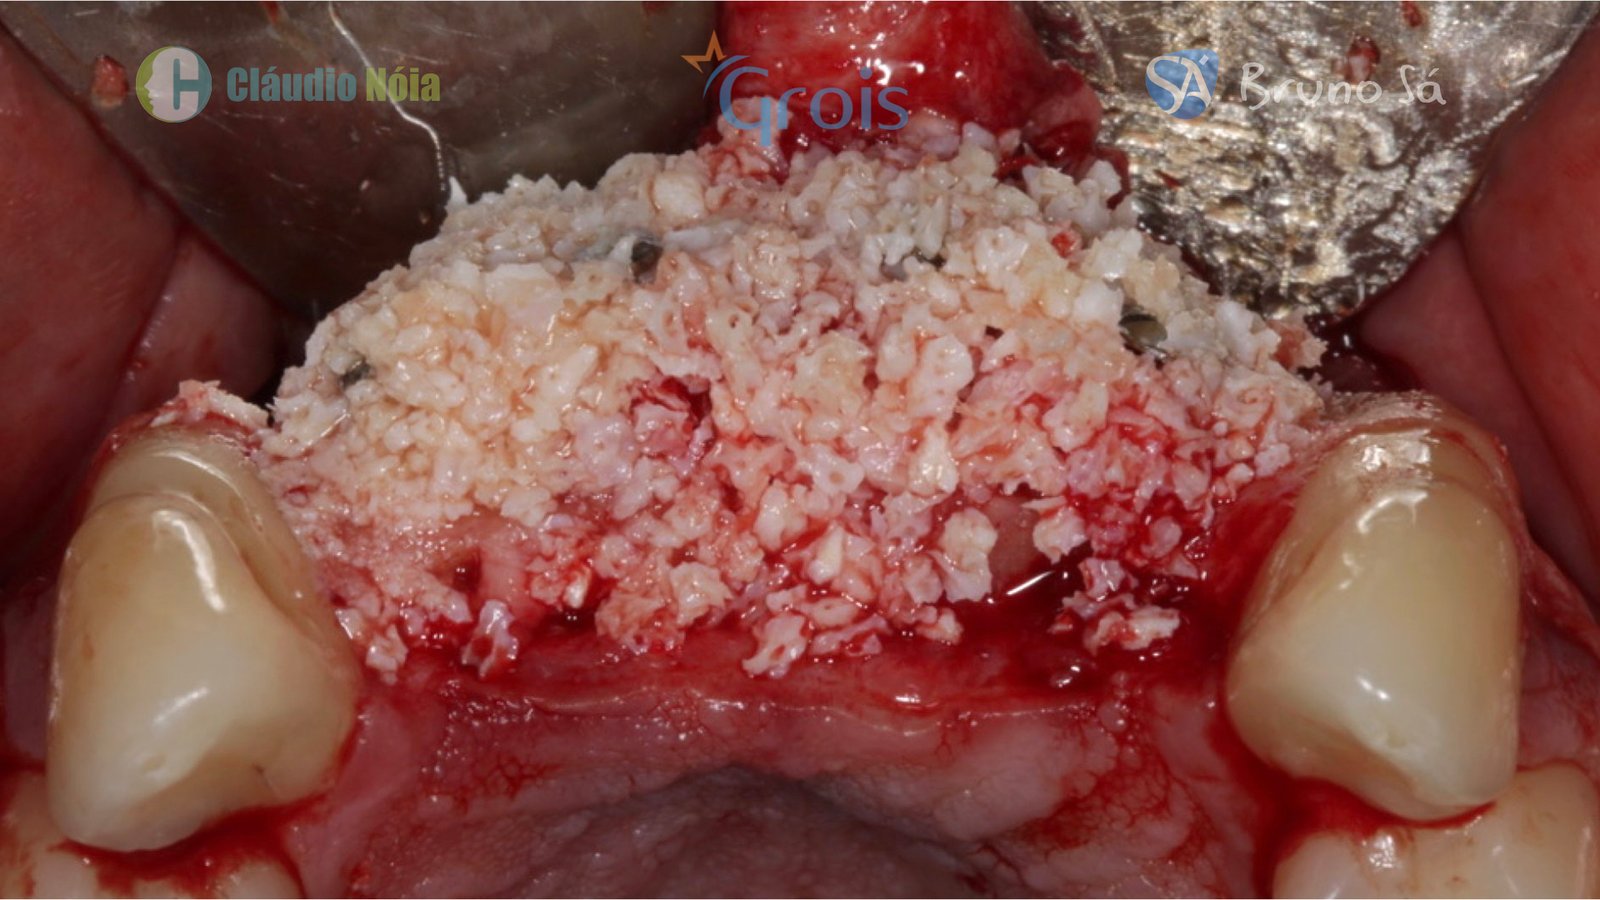

Para realização da técnica Screw Tent Pole são utilizados parafusos que funcionam como tenda para suportar o tecido mole, bem como são utilizados biomateriais e membrana de colágeno (ou Fibrina Rica em Plaquetas-PRF) visando promover a neoformação óssea.

Paciente apresentou-se a Área de CBMF da Instituição com a pré-maxila edêntula (Figuras 1, 2 e 3) e foi submetido a técnica Screw Tent Pole utilizando os parafusos da linha Orth – Implacil de Bortolli (Figura 3). Do lado direito da pré-maxila foram instalados 3 parafusos que apresentavam roscas em toda superfície, enquanto que do lado esquerdo foram instalados 3 parafusos que não apresentam roscas no terço cervical (Figuras 4, 5, 6, 7 e 8). Biomaterial associado com PRF (Stick Bone) foi adequadamente acomodado na região e recoberto por membranas de PRF (Figuras 9, 10 e 11). Uma sutura livre de tensão foi realizada para finalizar o procedimento cirúrgico (Figuras 12 e 13).